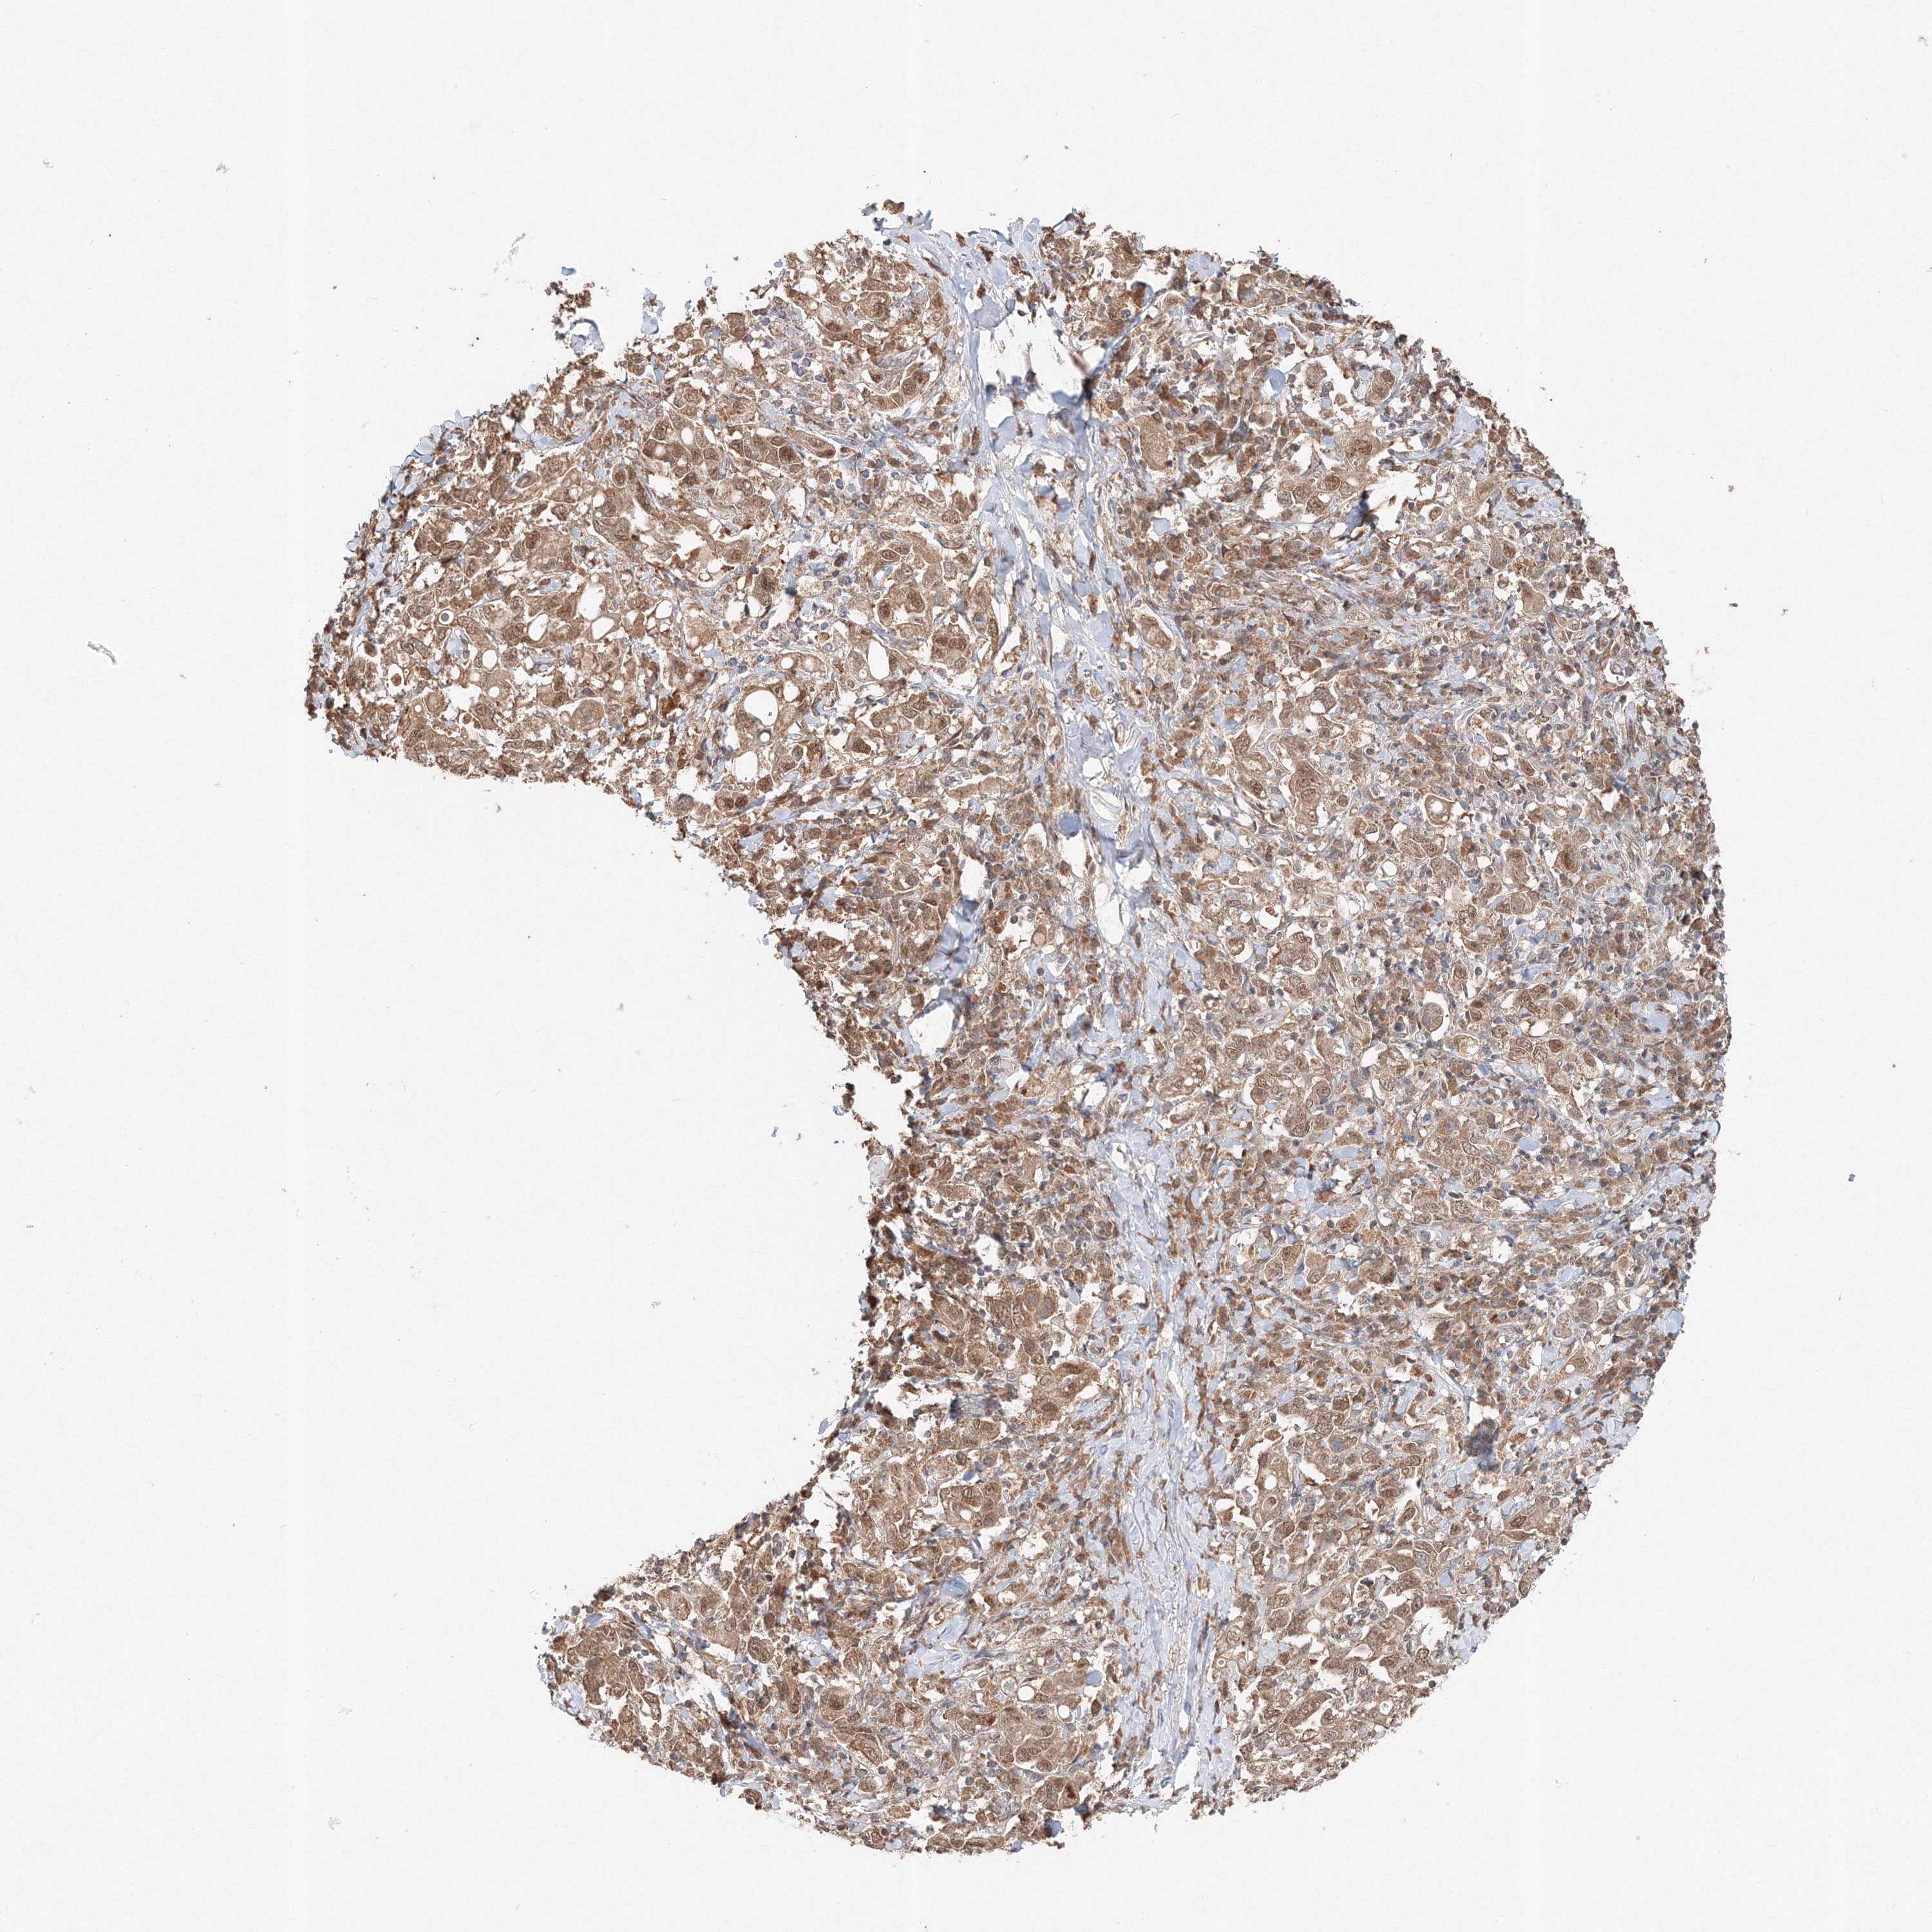

STOMACH CANCER - Protein expressioni

A mouse-over function shows sample information and annotation data. Click on an image to view it in a full screen mode. Samples can be filtered based on level of antibody staining by selecting one or several of the following categories: high, medium, low and not detected. The assay and annotation is described here.

Note that samples used for immunohistochemistry by the Human Protein Atlas do not correspond to samples in the TCGA dataset.

Antibody stainingi

Antibody staining in the annotated cell types in the current human tissue is reported as not detected, low, medium, or high, based on conventional immunohistochemistry profiling in selected tissues. This score is based on the combination of the staining intensity and fraction of stained cells.

Each image is clickable and will lead to virtual microscopy that enables deeper exploration of all samples and also displays staining intensity scores, fraction scores and subcellular localization as well as patient and tissue information for each sample.

Antibody HPA036921

Antibody HPA036922

Staining

High

Medium

Low

Not detected

Intensity

Strong

Moderate

Weak

Negative

Quantity

>75%

75%-25%

<25%

None

Location

Nuclear

Cytoplasmic/membranous

Cytoplasmic/membranous,nuclear

Adenocarcinoma, NOS